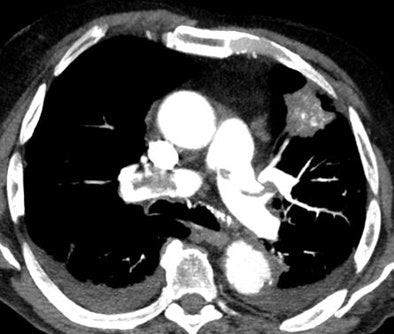

| Axial image shows extensive filling defects in the pulmonary trunk and the main pulmonary arteries. A solid lesion is seen in the left lung. Bilateral pleural effusion is also present. All images courtesy of Dr. Giulia Zamboni. |

The results showed PE in 73 (30.5%) of 239 patients; of these cases, 45 (61.6%) were categorized as massive and 28 (38.4%) as nonmassive.

Collateral findings in patients with PE included pleural effusion (n = 27), parenchymal consolidation (n = 15), and tumors (n = 7). In 165 scans that were negative for PE, 75 patients had no significant findings at CT and 90 had pleural effusion (n = 66), parenchymal consolidation (n = 36), or tumors (n = 10).